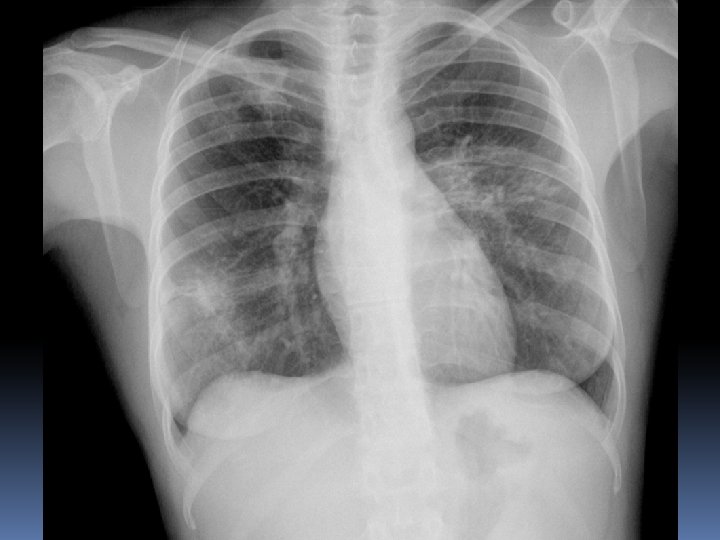

X 2007 Mujer 26 años Astenia, adelgazamiento 5 kg en 3 -4 meses. Nerviosa. Problemas de pareja. Hace 15 dias : tos seca y dolor en costado izquierdo por lo que acude a Urgencias del hospital. No fiebre termometrada. Dolor en costado Izquierdo de características pleuríticas. Auscultación normal. Sat 98%.

Un mes mas tarde……. .